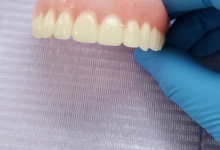

Clinica LUY ESTHETIC ART dispune de ultimele tehnologii in domeniul stomatologic si ofera solutia tratamentelor endodontice, pentru a incerca sa salveze un dinte care a fost distrus in proportii mari. Specialistii nostrii efectueaza acest tratament in mod corespunzator, pentru a evita aparitia altor complicatii ce implica interventii mai complexe: rezectia apicala sau riscul de a pierde dintele.

La Clinica LUY ESTHETIC ART tratamentul endodontic poate fi efectuat pe durata mai multor sedinte, doar cand chisturile dezvoltate sunt medii. Tratamentul nu este dureros deoarece se realizeaza sub anestezie. Pe langa talent, cunostinte medicale, dar si meticulozitate, acest tratament, presupune folosirea unei aparaturi performante: